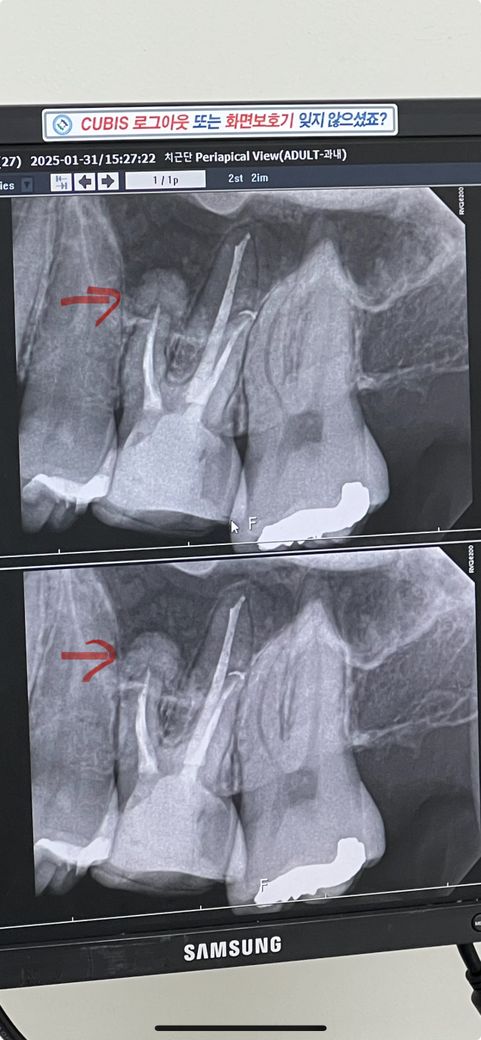

대학병원에서 치아 신경치료 4차까지 받고 5차에 마무리(1/31)하고 크라운 작업까지 마쳤습니다..

저는 흰색으로 혹? 같은 뭐가 있습니다.. 이게 뭘까요?..

간혹 치아 뿌리 끝에 염증이 생겨서 뼈가 생긴다면 그 염증이 치유되면서 여러가지 조직으로 바뀌는데요, 가장 이상적은 것은 골조직으로 치환되는 것이고 두번째로는 섬유성조직으로 치환되서 까맣게

보이는 것이고 세번째로는 저렇게 경조직으로 치환되어 하얗게 보이는 것 인데요.

통증이 없다면 사실 문제는 없지만 계속 통증이 있다면 치근단 절제술을 시행해야 할 수도 있습니다. 다만 사진상으로 보기에

상악동과 겹쳐보여서 수술 할때도 조금 어려움이 있을 것 같습니다.

신경치료는 잘된 것으로 보입니다. 치아뿌리 끝에 둥글게 보이는 것은 뼈가 겹쳐서 일 경우나, 치아뿌리에 붙은 일종의 과증식(예를 들면 백악질종, 골종)일 수 있습니다. 그러나 시간이 지나면 통증이 없어지는 경우가 대부분입니다. 만약 계속 통증이 있어 못씹을 정도라면 치근단 절제술 생각해야 합니다.

치근단 부위에 염증이 심한 경우에는 신경치료에도 통증이 남아 있는 경우가 있습니다. 대부분 이런 불편감은 시간이 지나면서 괜찮아지는 경우가 많으며 그렇지 않을 경우에는 치근단 절제술을 해야 하는 경우도 있습니다. 뿌리 끝에 하얗게 보이는 것은 치코용 재료로 큰 문제를 발생시키지 않기 때문에 걱정하지 않으셔도 됩니다